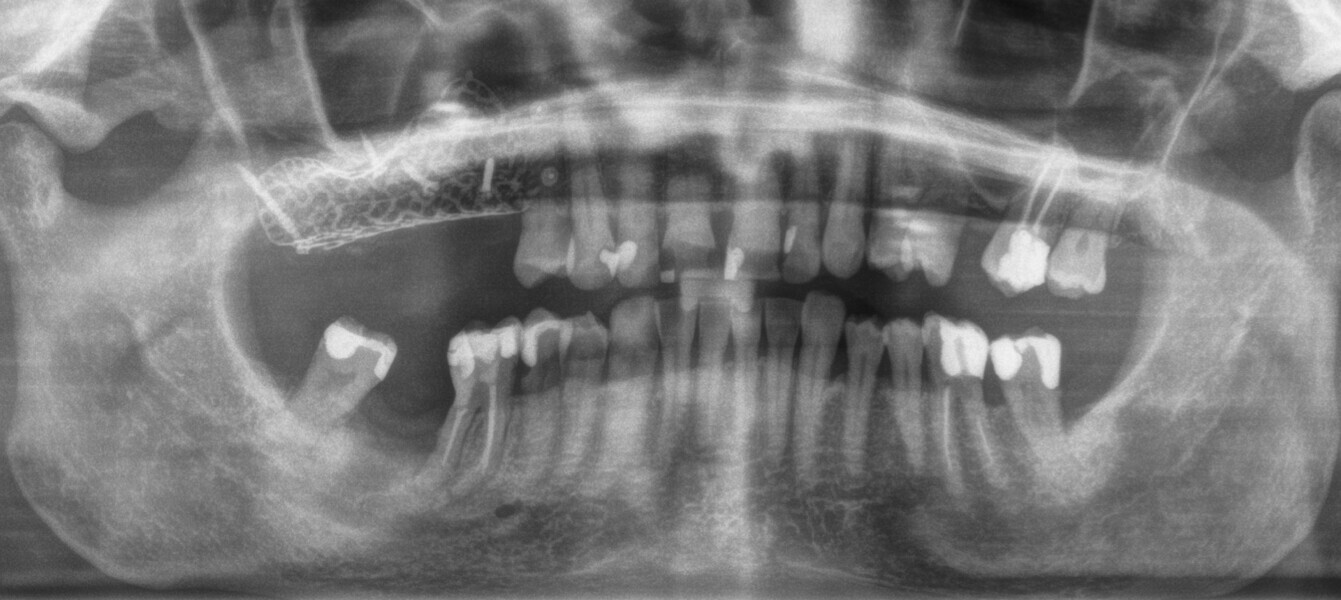

Subsequently, the surgical guide was placed and fixed in the planned position, the implant sites were prepared with progressive dedicated drills and three conical implants (T3, ZimVie) were placed in sites #15, 16 and 17 according to the prosthetically guided plan obtained from the guided surgery software (Figs. 29, 30a-c, 31a & b). The implants were covered to allow for proper osseointegration, and first intention closure was performed (Figs. 32a & b). After implant placement, a dental panoramic tomogram was taken (Fig. 33).

After three months, the implants were exposed through an apically positioned flap to increase the amount of keratinised tissue on the vestibular side of the implants and to realign the mucogingival junction, previously shifted towards the palate. Flared healing screws were placed to promote proper transmucosal healing. After one month, single ceramic crowns were placed for the first functional loading and temporary restoration while waiting for complete bone maturation (Fig. 34). After six months, the crowns were replaced with zirconia crowns for the final functional loading and the definitive restoration (Figs. 35–38). Clinical and radiographic follow-ups at the first functional loading, at six months, 12 months and 24 months showed the health of the peri-implant tissue and the maintenance of peri-implant bone levels (Figs. 39a-d).